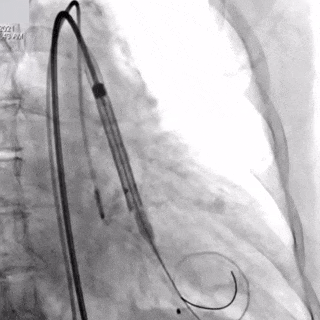

TaurusNXT植入过程:

瓣膜第一次展开与回收

瓣膜再次定位与展开

瓣膜稳定释放

TaurusNXT为全新一代干瓣预装载经导管主动脉瓣系统,在瓣叶生物化处理上采用国际领先的非戊二醛技术,避免了残留醛基诱发组织钙化,机制上消除了钙化的主要风险,并且在复合交联、除原体细胞、抗降解性能、病毒去活等全方位提升了生物瓣叶的性能,以期带来更优越耐久性和更好的生物相容性。此外,有别于传统的甘油处理技术,采用国际首创的低温冻干技术的瓣叶干式处理,完整保持了瓣叶物理性能,同时实现瓣膜系统的预装载。TaurusNXT输送器采用的专利导管设计,在不牺牲过弓柔顺性的同时确保可靠稳定的回收性能,并增加远端调弯功能,改善瓣膜与主动脉的同轴性,进一步提升过弓跨瓣能力,可安全有效的应对复杂主动脉弓及横位心等形态挑战,改善同轴性。